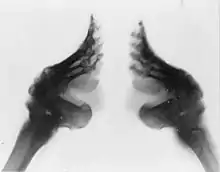

An X-ray of two bound feet

Schema of an X-ray comparison between an unbound and bound foot